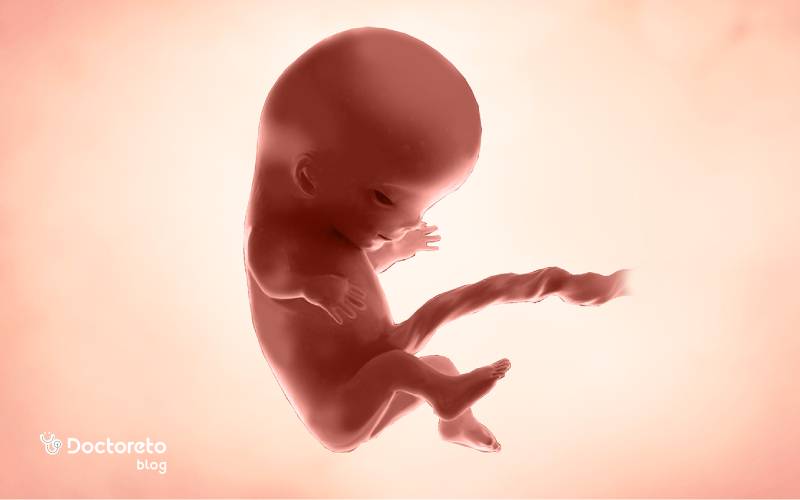

در جنین ۱۱ هفتهای، نسبت سر به بدن هنوز بزرگتر است اما گردن مشخصتر شده و بدن از حالت خمیده ابتدایی خارج میشود. انگشتها و انگشتان پا از هم جدا شدهاند، مفاصل زانو و آرنج فعالترند و جوانههای دندانی اولیه شکل گرفتهاند. کبد هنوز نقش پررنگی در خونسازی دارد و رودهها که تا همین حوالی در بند ناف بودند، بهتدریج به داخل شکم برمیگردند. شکل جنین در هفته یازدهم بارداری در سونوگرافی با ستون فقرات روشن و حرکات جهشی کوتاه قابلمشاهده است.

از نظر عملکرد، مسیرهای عصبی و مخچه رشد میکنند و همین باعث افزایش حرکات بازتابی میشود. بااینحال شما هنوز این حرکات را حس نمیکنید. پوست جنین نازک و نیمهشفاف است و عروق زیر آن دیده میشوند. استخوانسازی جنین 11 هفته آغاز شده و استخوانهای بلند پا و ساعد در تصاویر سونو نمایانترند. همه این تغییرات جنین ۱۱ هفته ای زمینه جهش رشدی سهماهه دوم را فراهم میکند. مهمترین تغییرات جنین در هفته یازدهم حاملگی عبارتند از:

شکل جنین در هفته یازدهم بارداری متقارنتر میشود؛ صورت با نزدیکی تدریجی چشمها به خط میانی، تشکیل پلکهای بسته و مشخصتر شدن بینی و لب بالا دیده میشود. انگشتان دست و پا شکل میگیرند و ناخنها تشکیل میشوند. دست و پای قورباغهای در این هفته بهطور کامل از بین میروند و جنین شبیه به نوزاد میشود. دستها در مچ خم میشوند، پاها کشیدهتر شدهاند و حرکات لگد مانند کوتاه در سونوگرافی مشاهده میشود. طنابنخاعی و مهرهها بهصورت خطوط روشن موازی مشخصاند. جنین تقریبا اندازه یک انجیر است.